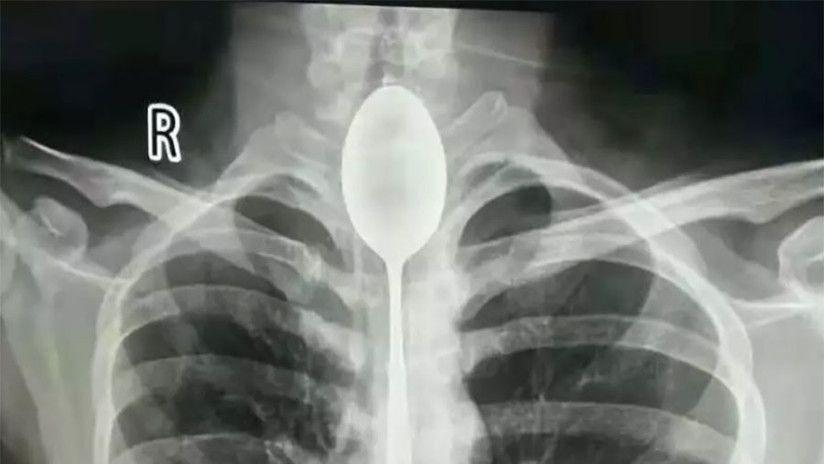

Médicos chinos tuvieron que sacar una cuchara de 20 centímetros que estuvo atorada durante un año en el esófago de un joven.

En una cosa Zhang tuvo suerte: no se necesitó intervención quirúrgica para sacarle el cubierto. Luego de realizarle una radiografía, los médicos extrajeron el objeto metálico al paciente de 26 años por vía bucal. Todo ese tiempo, un poco más de dos horas, el joven estuvo totalmente anestesiado, según un comunicado del hospital.